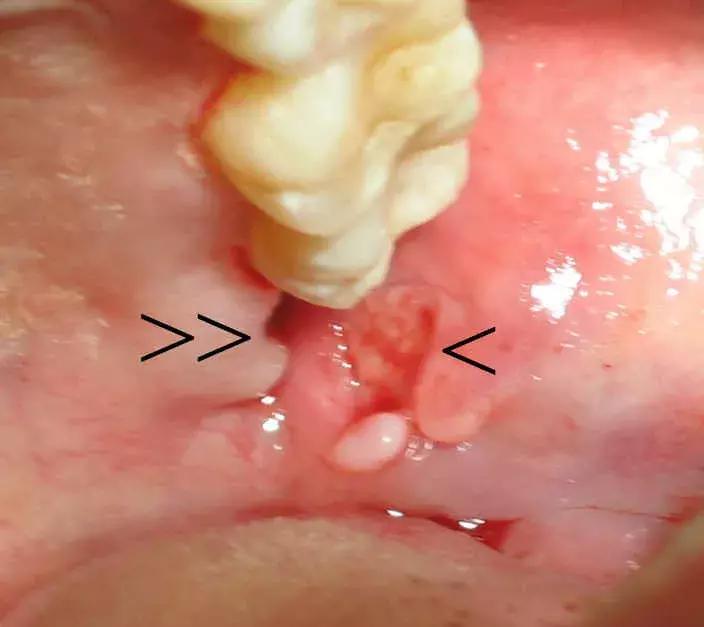

不是持续的胀痛,是那种反反复复红肿,特别磨人↓

真相是,它真的就到这为止了,就露个尖儿↓